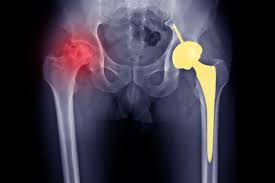

When AVN progresses or non-surgical treatments are insufficient, surgical intervention becomes necessary. Procedures may include core decompression, bone grafting, or total joint replacement, depending on the severity and location of bone damage. Under the supervision of Dr. Utsav Agrawal, Varunam Hospital performs surgeries with precision, following modern protocols to ensure optimal outcomes. Moreover, advanced surgical techniques minimize recovery time, reduce complications, and restore joint function for Gadchiroli patients.

Recovery after AVN surgery is critical for long-term success. Varunam Hospital provides structured post-operative care, including pain management, wound care, and physiotherapy. Dr. Utsav Agrawal emphasizes early mobilization and guided exercises to restore joint strength, flexibility, and range of motion. In addition, personalized rehabilitation plans reduce complications and improve functional outcomes. Therefore, comprehensive post-operative care ensures patients regain mobility and confidence in daily life.

Effective AVN treatment significantly improves quality of life by reducing pain, restoring mobility, and preventing joint collapse. Patients in Gadchiroli who receive care at Varunam Hospital benefit from durable outcomes and long-term joint preservation. Moreover, precise surgical techniques and tailored rehabilitation under Dr. Utsav Agrawal ensure that treated joints remain functional for years. As a result, patients can resume normal activities and maintain independence.